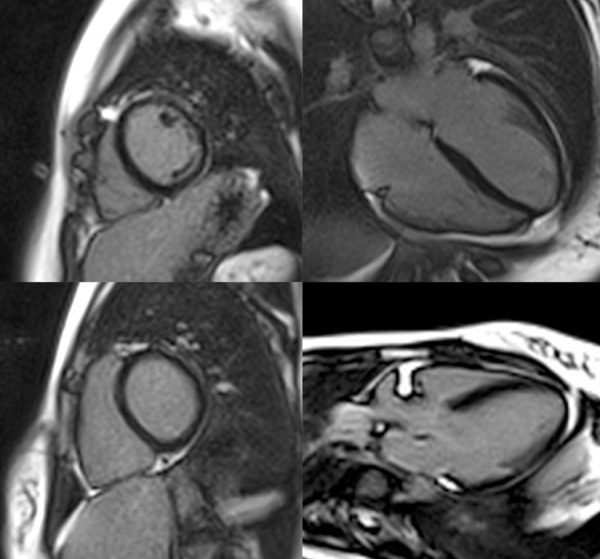

Peripartum cardiomyopathy (PPCM) is a potentially life-threatening condition that can occur during the late pregnancy or puerperium. A 31-year-old woman with a recent twin pregnancy presented with heart failure symptoms nine days postpartum. On admission, she had volume overload and hemodynamic compromise, which was rapidly reversed with inotropic levosimendan support. Echocardiography revealed a left ventricular ejection fraction (LVEF) of 20% with global hypokinesia. Once stabilized, she was discharged on heart failure medication, bromocriptine, and warfarin. Cardiac magnetic resonance imaging at five weeks demonstrated a preserved LVEF of 57% and no evidence of myocardial scarring or edema. During the 4-year follow-up, the patient remained stable with no new pregnancies. This case highlights the importance of considering PPCM in the differential diagnosis of heart failure in the peripartum period after excluding other etiologies. It also describes the successful use of bromocriptine in facilitating recovery of systolic function without long-term complications.